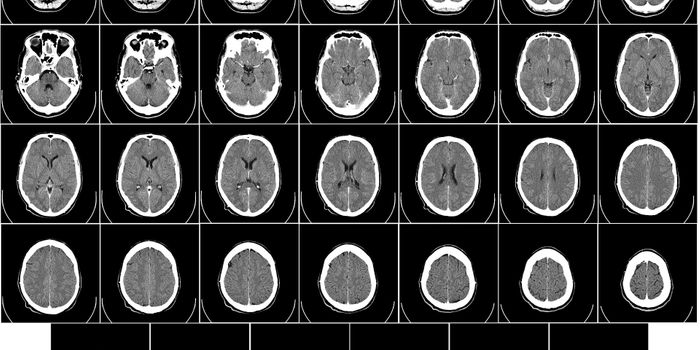

DEC 03, 2020NeuroscienceTo obtain high-resolution images of the brain, researchers usually need to reduce the thickness of the skull or cut into ...